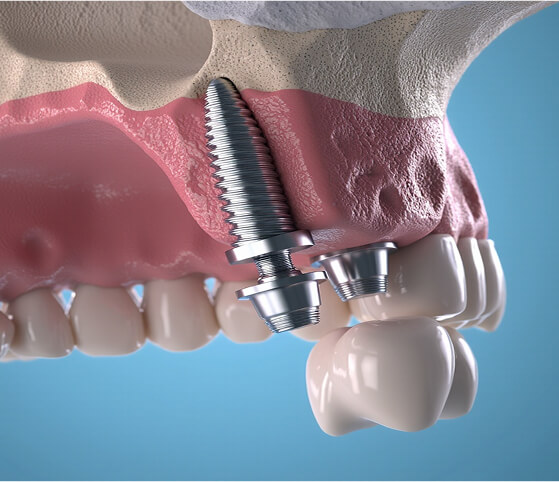

Ahogy a saját fogát, úgy az implantátumot is a csont tartja a megfelelő, stabil pozícióban. Emiatt fontos, hogy az implantáció a lehető leggyorsabban megtörténjen a fog elvesztése – és a seb gyógyulása – után. Ahogy az is fontos, hogy az implantátum erős alapra épüljön.

A csontpótlás biztosítja a megfelelő csontszélességet és vastagságot, hogy az implantátumok behelyezhetők legyenek, stabilan rögzüljenek.

Az újonnan képződő, élő csontszövet elősegíti az állcsont egészséges működését, az implantátumokon keresztül megelőzi annak további sorvadását, és hosszú távú eredményt biztosít.